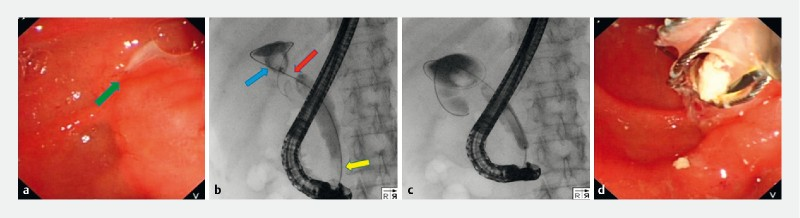

团队完成了一例特殊的ERCP下“网篮嵌顿”患者的内镜下诊治。该患者为57岁女性,20年前因“胆结石”接受了胆囊切除术、胆总管切开探查术和胆肠吻合术治疗,现因怀疑存在胆总管结石、外院取石失败而转诊至我院行ERCP经内镜胆管取石术。术中发现在十二指肠乳头开口处有脓液流出,胆管造影提示胆总管和吻合口处分别存在充盈缺损。胆管插管成功后尝试使用网篮取石(图1)。然而,取石网篮套住充盈缺损后发生嵌顿,反复尝试无法取出。由于插入的网篮无法收回,患者存在被动接受急诊外科手术取出网篮的风险。由于患者曾行胆肠吻合术即消化道改道,团队尝试从改道后另一消化管腔中查看情况。当即换用小肠镜进镜至胆肠吻合口处,见网篮套住部位并非胆管结石,而是一处直径约2 cm的黏膜隆起。随后,在直视下通过活检钳松解,成功取出嵌顿的网篮(图2),并在黏膜隆起处取样本活检,术后病理提示为慢性炎症。

图1 1a.可见脓液从十二指肠乳头开口处流出(绿色箭头所示);1b.胆管造影分别显示胆管下段和吻合口(分别以蓝色和黄色箭头表示)充盈缺损,同时提示吻合口狭窄(如红色箭头所示);1c、d .尝试网篮取石